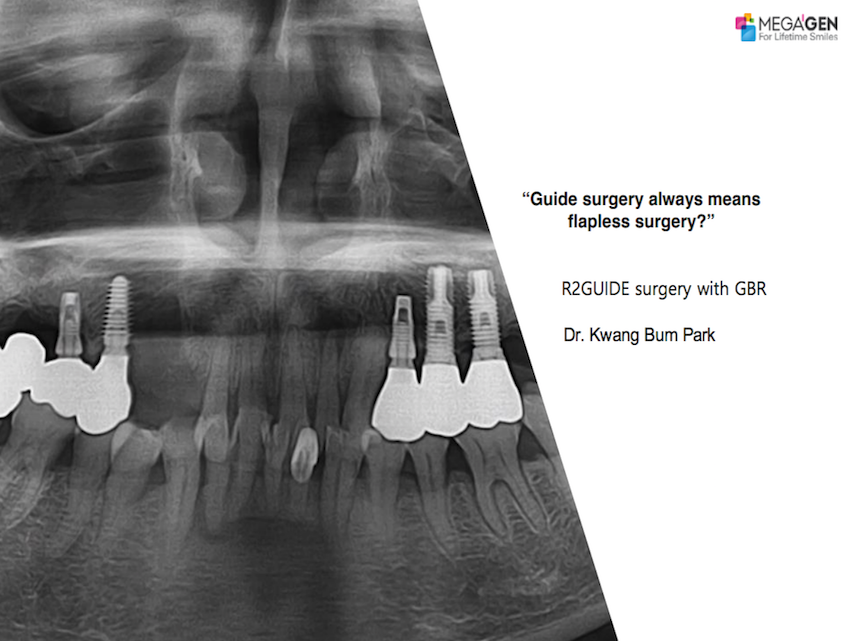

Guide surgery always means flapless surgery?

Dr. Kwang Bum Park,Digital Guided Surgery,Maxillary Anterior,#13,#14,Flapless,AnyRidge,R2GATE,AnyRidge Surgical Kit